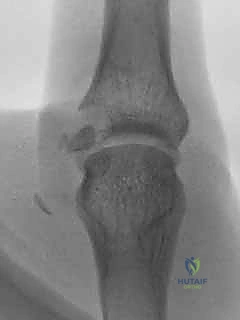

تحرير تيبس المرفق بتقنية العمود الجانبي: استعادة حركة ذراعك مع الأستاذ الدكتور محمد هطيف

هل تعاني من تيبس المرفق؟ تعرف على عملية تحرير العمود الجانبي المتقدمة لاستعادة حركة ذراعك. الأستاذ الدكتور محمد هطيف خبير جراحة العظام في ص…

تحرير تصلب الكوع بتقنية "فوق القمة الإنسية": استعادة حركة الذراع مع الأستاذ الدكتور محمد هطيف

استعد حركة كوعك الطبيعية مع الأستاذ الدكتور محمد هطيف في صنعاء. تعرف على تقنية تحرير تصلب الكوع "فوق القمة الإنسية" المتقدمة، علاج فعال لمح…